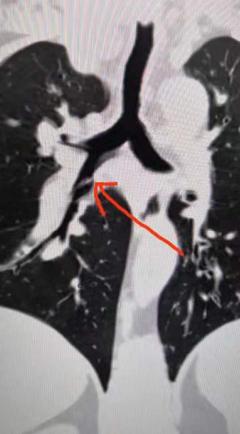

1月23日,59岁的鲍先生满脸焦虑地来到景德镇市第三人民医院呼吸与危重症医学科门诊就诊。此前,鲍先生反复咳嗽、咳痰已2月余,在他自行服用感冒药及抗生素后,症状依然未见好转,在外院进行胸部CT提示右肺中下叶开口处有异物,经家人介绍,慕名前来市第三人民医院就诊。

市三院呼吸与危重症医学科副主任医师江焰平接诊后,根据丰富的临床经验分析,患者咳嗽病程长,胸部CT提示异物阻塞,看形状很可能是某种动物的骨头,这可能才是导致鲍先生反复咳嗽、咳痰迁延不愈的真正原因。经过仔细询问鲍先生及其家属得知,鲍先生平素进食速度快,咀嚼不仔细,并于2月前食用“黄芽头”后有呛咳情况,但很快好转,所以没有考虑过误吸可能。

1月25日,科室主任、主任医师黄国民,副主任医师江焰平,护士长曹晖红,主管护师毛景丹等人密切协作,为鲍先生进行了手术,通过电子支气管镜准确找到了异物阻塞的位置,并成功取出了一根长约2cm的锯齿样鱼刺,与之前患者及家属回忆的情形相一致,终于确定了鲍先生长期咳嗽不愈的病因。1月27日,鲍先生的病情恢复良好并出院。